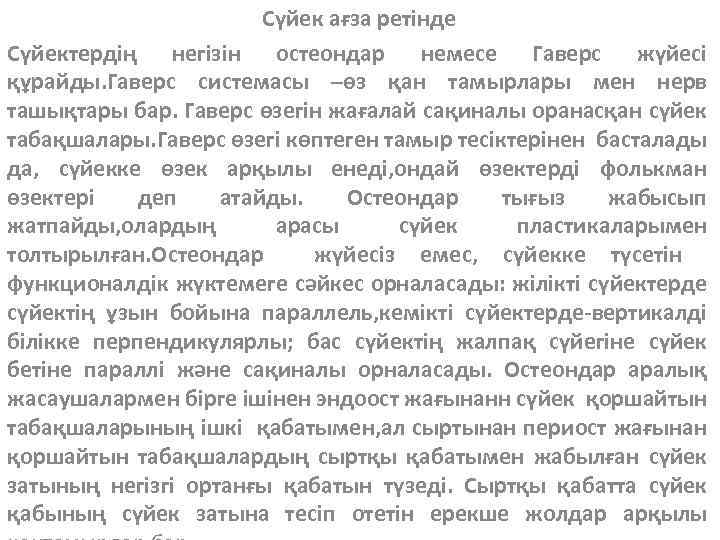

Сүйек ағза ретінде Сүйектердің негізін остеондар немесе Гаверс жүйесі құрайды. Гаверс системасы –өз қан тамырлары мен нерв ташықтары бар. Гаверс өзегін жағалай сақиналы оранасқан сүйек табақшалары. Гаверс өзегі көптеген тамыр тесіктерінен басталады да, сүйекке өзек арқылы енеді, ондай өзектерді фолькман өзектері деп атайды. Остеондар тығыз жабысып жатпайды, олардың арасы сүйек пластикаларымен толтырылған. Остеондар жүйесіз емес, сүйекке түсетін функционалдік жүктемеге сәйкес орналасады: жілікті сүйектерде сүйектің ұзын бойына параллель, кемікті сүйектерде-вертикалді білікке перпендикулярлы; бас сүйектің жалпақ сүйегіне сүйек бетіне параллі және сақиналы орналасады. Остеондар аралық жасаушалармен бірге ішінен эндоост жағынанн сүйек қоршайтын табақшаларының ішкі қабатымен, ал сыртынан периост жағынан қоршайтын табақшалардың сыртқы қабатымен жабылған сүйек затының негізгі ортанғы қабатын түзеді. Сыртқы қабатта сүйек қабының сүйек затына тесіп отетін ерекше жолдар арқылы

• келетін қантамырлар бар. Қантамырлар сүйектегі зат-алмасуды қамтамасыз етеді. Жәй көзбен көрінетін сүйектің ірілеу элементтері-сүйек затының аралық шабақтары немесе трабекулалар остеондардан тұрады: 1 -тығыз тұтас заттрабекулдер тығыз жатқанда-substancia compacta. 2 -кеукті заттар-трабекулдер бостау жатады-substacia spongiosa. • Тығыз және кеуек заттардың таралуы сүйектің қызыметтік жағдайларына байланысты болады. Тығыз зат негізінен тірек және қозғалыс үшін қажет. Ал кеуек заттар жілік сүйектердің эпифиздерінде болады. Қорғаныс қызыметі атқаратын бас сүйектер үш қабаттан тұрады: сыртқы табақша, ішкі табақша, арасынды кеуек зат -диплое. Сүйек уяшықтарында жілік майы-қан жасау және организмдегі биологиялық қорғау ағзасы болады. Ол сүйектің қоректену мен дамуына және өсуіне қатысады. Жілік сүйектерде жілік майы осы сүйектердің қуысында болады, сондықтан оны жілік май қуысы деп атайды. Жілік май қуысы жілік майымен толтырылған.

Жілік майы екі түрлі болады: қызыл және сары. Қызыл жілік майы; торлы ттінннен тұратын нәзік қызыл масса түрінде болады, оның тұзақтарында қан жасалуына және сүйек жасалуына тікелей қатысты жасушалық элементер орналасады. Қантамырлар және қан элементері жілік майына қызыл түс береді. Сары жілік майы негізінен май жасаушаларынан тұрғанан кейін сары түсті болады. Іштегі нәресте және туған балада тек қызыл жілік майы болады. Бала өсе келе қызыл жілік майы бірте-бірте сары жілік майына аусысады да, ересек адамда тек сары жілік майы ғана болады. Сүйекті сыртқа жағынан сүйек қабымен жабылған. Ол екі қабаттан тұрады: сыртқы және ішкі сүйек түзуші қабаттардан тұрады. Сүйек қабығы нервтер мен қантамырларға бай, соның арқасында сүйектің қоректену мен қалыңдап өсуіне қатысады. Қоректену сүйек қабының қоректік тесікшелер арқылы өтетін тамырлар есебімен, ал сүйектің өсуі, сүйеккке жанасып жатқан қабатта орналасқан остеобластар есебінен іске асырылады.